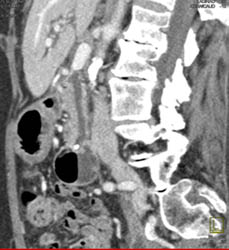

Cirrhosis